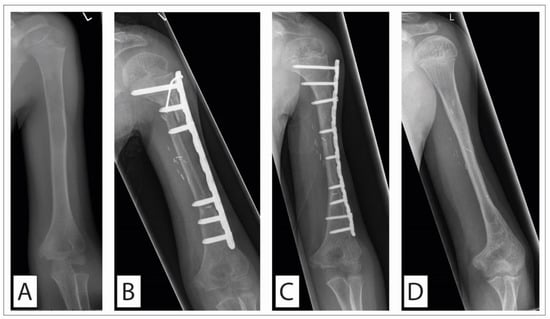

- Biological Reconstruction with Vascularized Grafts

- 2.

- Biological Reconstruction with Allografts and Capanna Technique